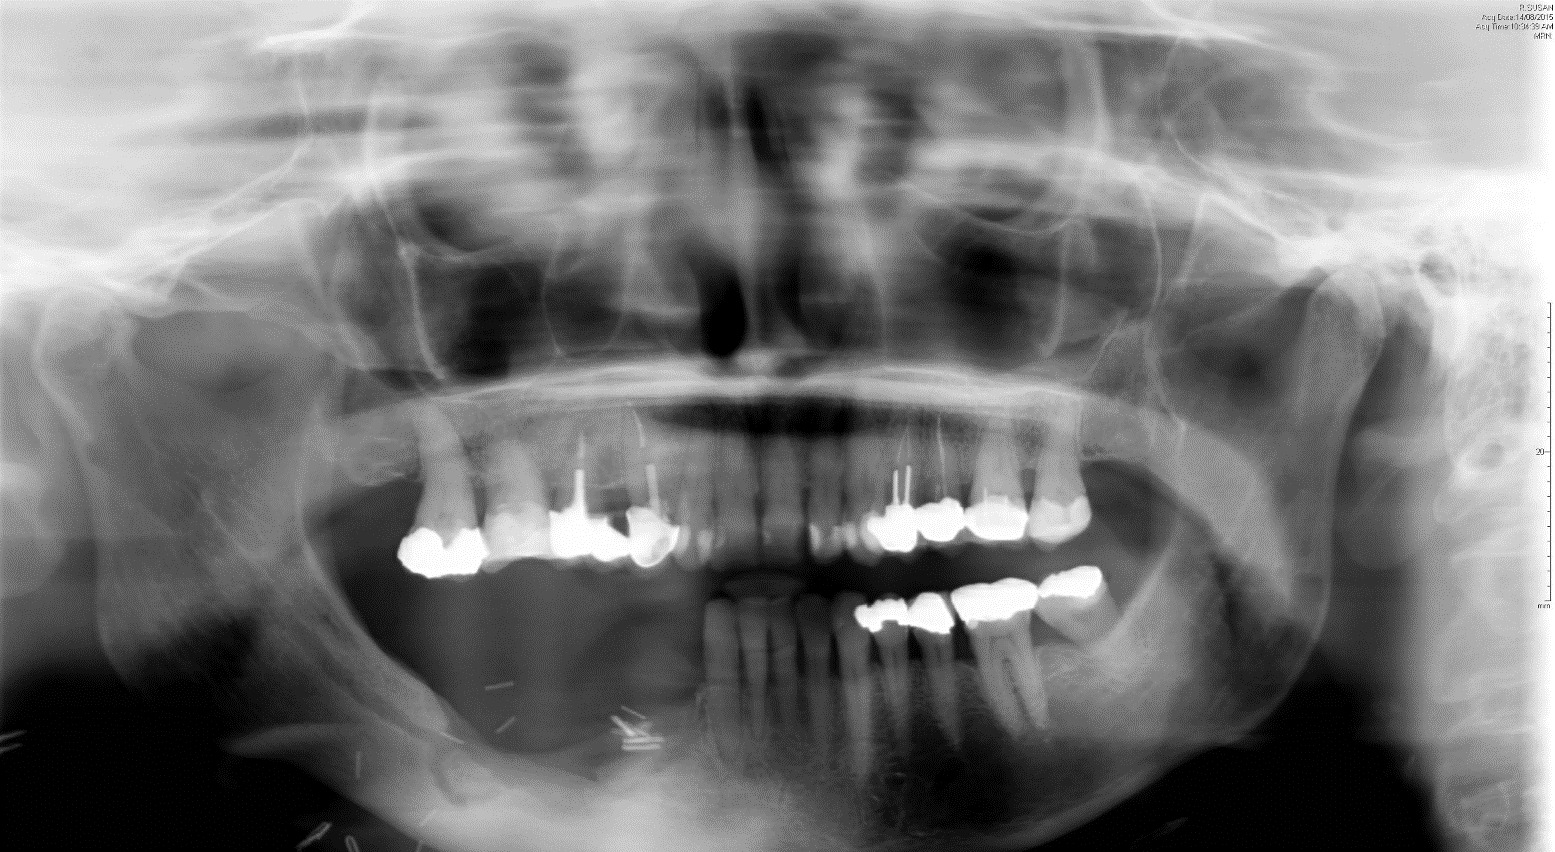

Four patients were managed with dental measures alone involving local debridement. Nasolabial flap reconstruction was selected for three patients. Vascularised periosteal (RFFF) reconstruction was selected for three patients. Patients were generally selected for local nasolabial flap reconstruction if the area of exposed bone was small and located in the maxilla or patients were deemed high risk for more complex longer surgeries due to comorbidities. Patients were selected for free periosteal forearm flap reconstruction if the area of necrotic bone was large, located in the mandible and if there was significant bone loss posing high risk for pathological fracture if disease were to progress (Figure 1). There were no postoperative complications recorded for the nasolabial flap or the RFFF patients.

Radiologically, three of the four patients managed with dental measures showed a mixed picture of increased bone loss at the site of previous debridement but with well-defined sclerotic margins at six months follow-up. The other of these four patients had two foci of MRONJ in the maxilla and mandible. The maxilla showed worsening bone erosion while the mandible showed sclerosis. Of the three patients selected for nasolabial flap, one demonstrated a mixed picture of interval bone loss but with well-defined sclerotic margins, one demonstrated an improved picture with increased bone and sclerotic margins and one patient did not undergo postoperative imaging. Due to symptom-free recovery, this patient did not consent to follow-up imaging. All three patients selected for RFFF demonstrated an improved radiological picture with increased bone deposition and well-defined sclerotic margins (Figures 3, 4, and 5).